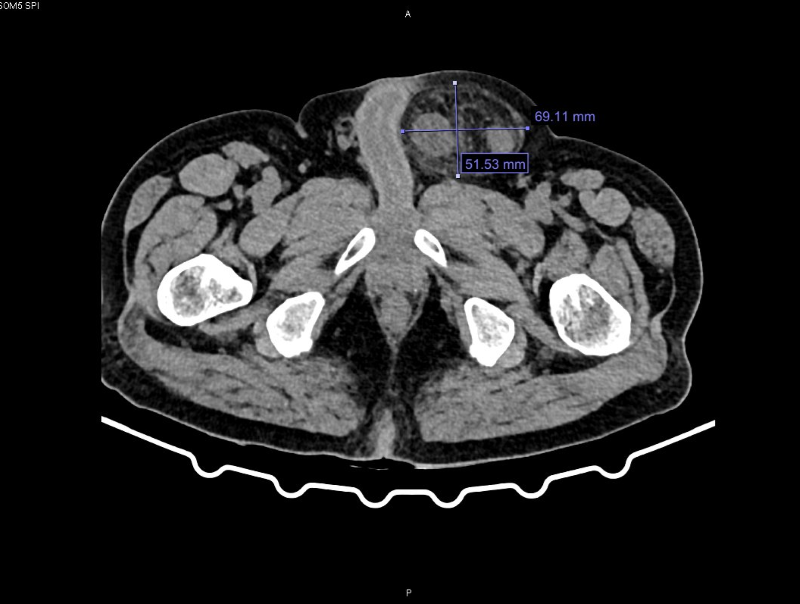

Qua thăm khám và chụp cắt lớp vi tính, các bác sĩ chẩn đoán bệnh nhân bị thoát vị bẹn trái nghẹt. Hội chẩn đánh giá đây là biến chứng phức tạp và nguy hiểm của thoát vị bẹn do ruột bị chui xuống lỗ thoát vị và kẹt lại gây tắc nghẽn, thiếu máu nuôi.

Hình ảnh khối thoát vị bẹn trái nghẹt qua phim chụp cắt lớp vi tính - Ảnh BVCC